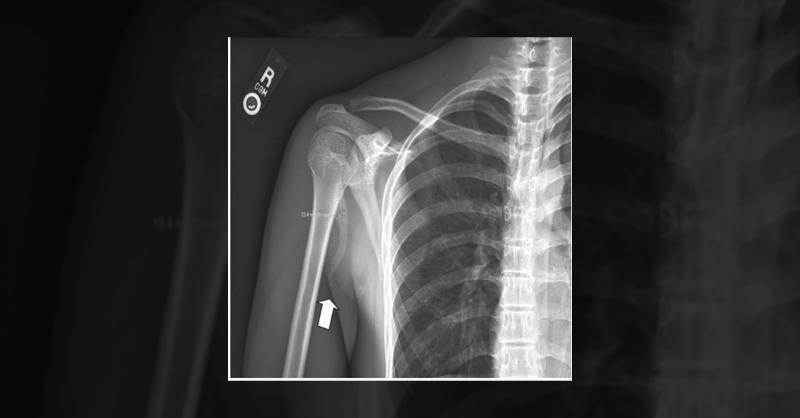

Managing Pectoralis Major Tendon Rupture Caused by Soccer Injury

A 16-year-old male presented with a two-month history of right anterior shoulder pain. The pain initially stemmed from a soccer injury where he landed on his right shoulder on a grass field. While the pain had been gradually improving, it was reaggravated during an attempt to throw a football. During the initial examination, the patient reported mo